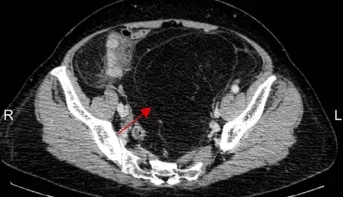

箭头示为患者一的腹膜后肿瘤

箭头示为患者二的腹膜后肿瘤